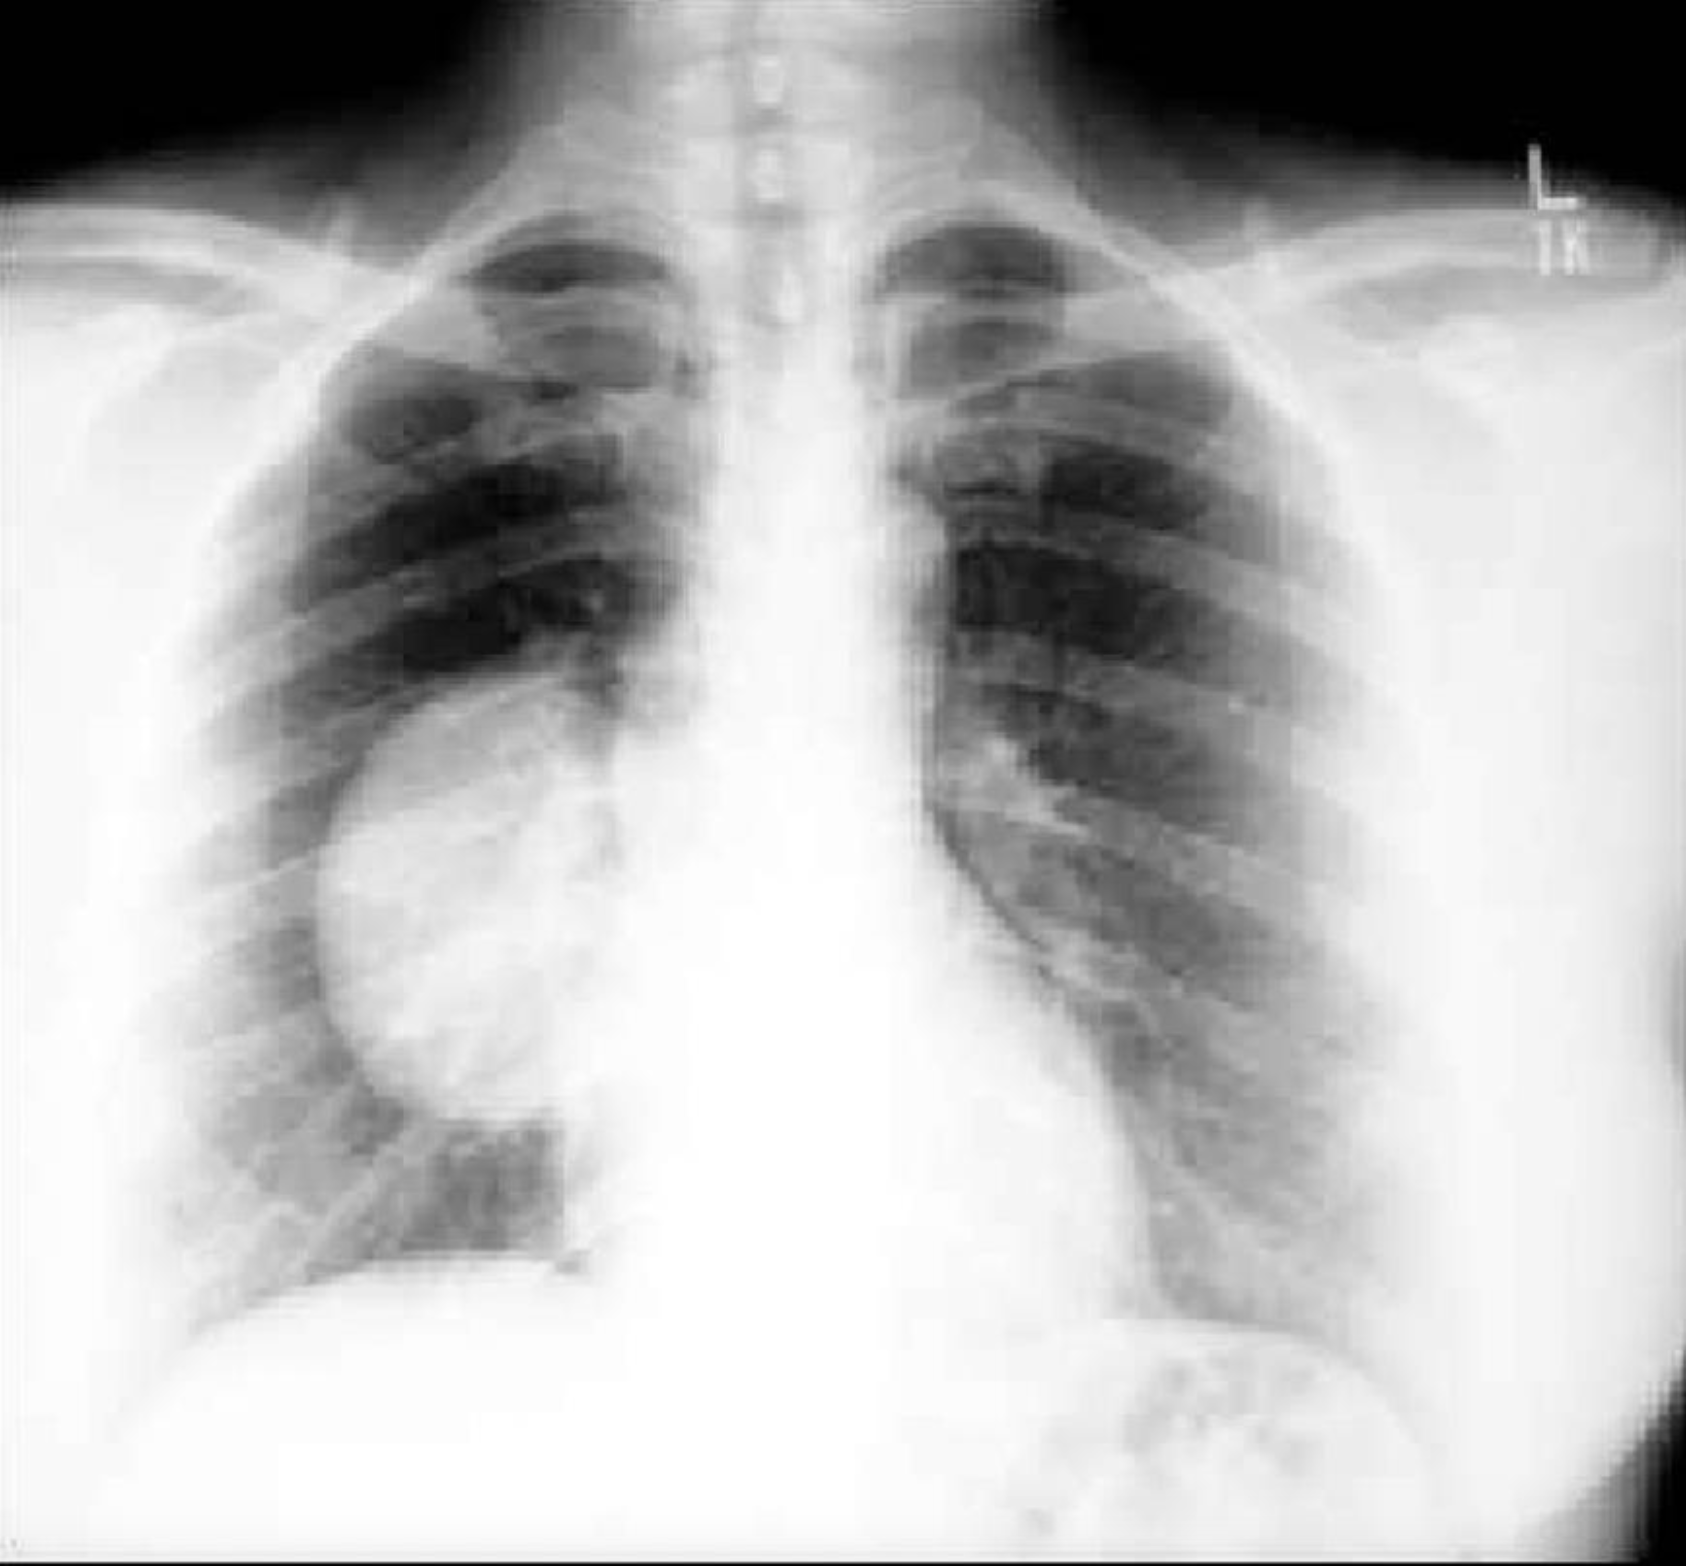

His chest X-ray is presented here.

How would you assess this patient preoperatively?

76.4%